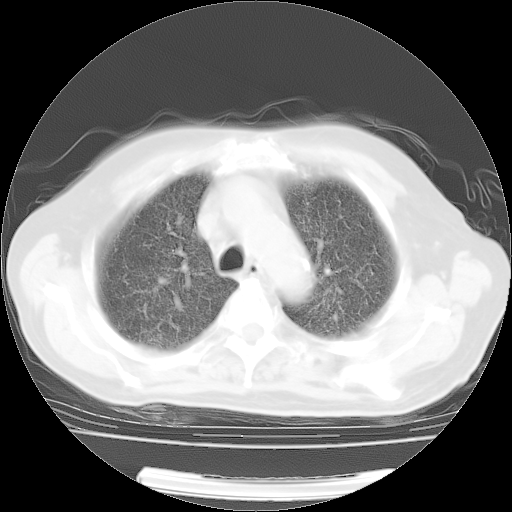

肺部CT平扫未见异常。